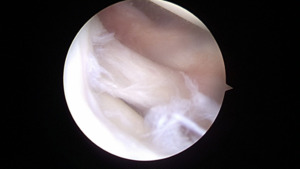

At the time of surgery, diagnostic arthroscopy revealed intact cartilage without any defects or abnormal wear. There was no evidence of a ligamentous injury. The medial meniscus was found to be intact (Figure 4).

The ACL and PCL were intact. The lateral compartment revealed a lateral meniscus tear with the tissue displaced centrally into the notch, impinging on the ACL (Figure 5).